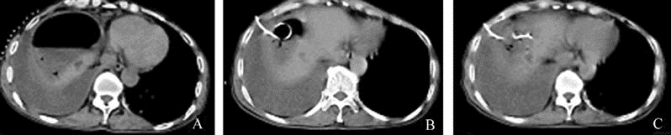

图21-38 膈下脓肿经皮抽吸引流

A.治疗前CT示右膈下巨大脓肿,内见气液平面;B.经皮穿刺置管冲洗引流术后1周,脓腔明显缩小;C.治疗后2周复查脓腔基本消失